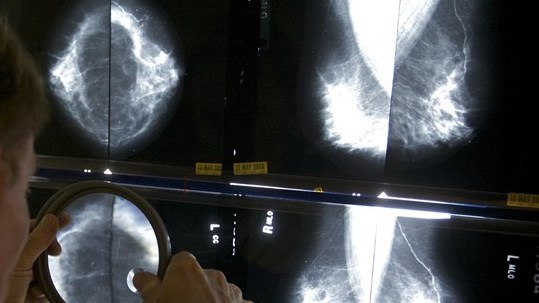

En 2020, de nombreux Américains ont été contraints à reporter leurs dépistages du cancer (coloscopies, mammographies et scintigraphies pulmonaires) de plusieurs mois, la COVID-19 ayant submergé médecins et hôpitaux.

Les taux de mortalité par cancer continuent de baisser, et il n'y a pas de changement majeur dans les diagnostics tardifs, selon un nouveau rapport publié lundi dans la revue Cancer.